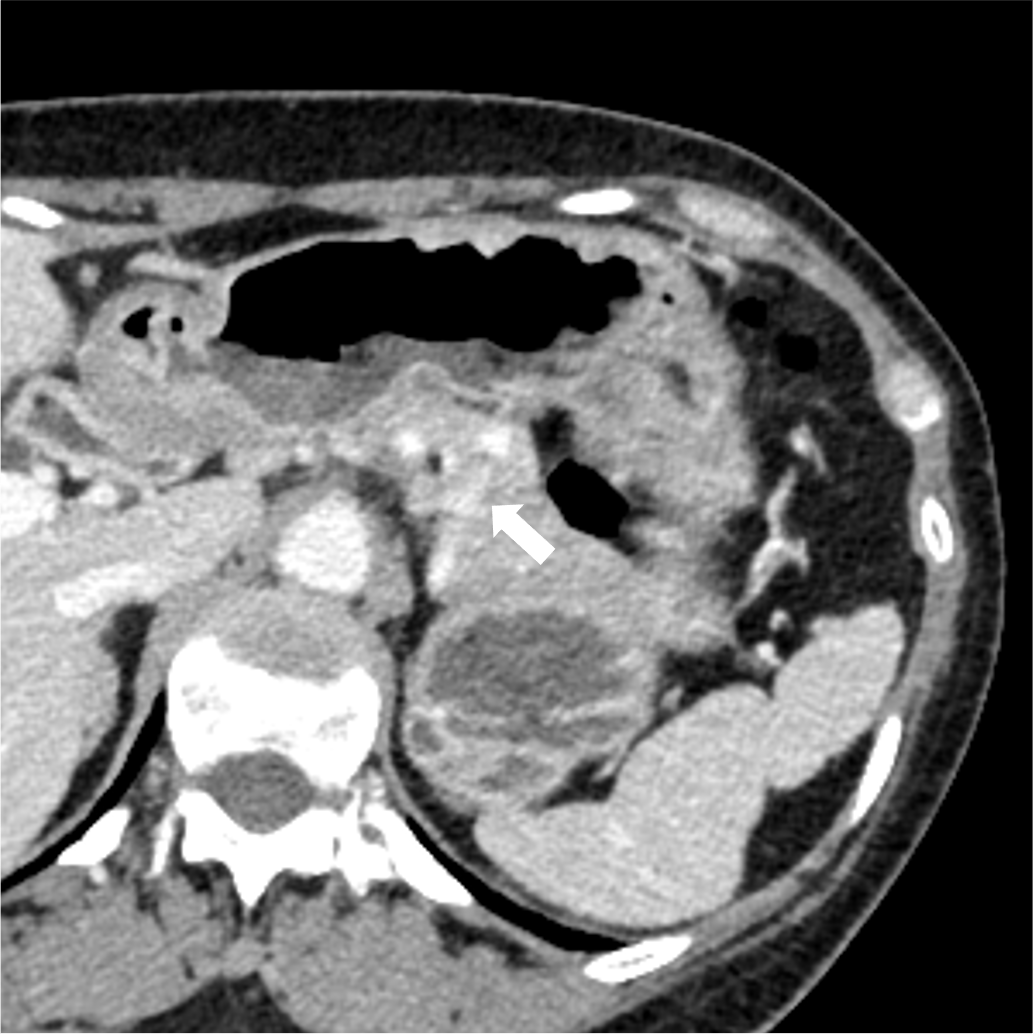

検診で指摘された肺病変のCT精査にて、肺の動静脈奇形(AVM)と診断された。精査および加療目的で当院に紹介され、術前精査のための造影CTを施行した。造影CTにて、膵尾部にAVMを認めた。その後、肺AVMに対するコイル塞栓術が施行され、その際に膵AVMも血管造影にて精査が行われた。膵AVMによる症状はなく経過観察とされ、外来にて定期的にフォローアップされている。

オスラー病(遺伝性出血性毛細血管拡張症、HHT)は、全身の血管に異常を生じる、常染色体優性遺伝の遺伝性疾患であり、特に肺・脳・肝臓・消化管などの動静脈奇形(AVM)や、鼻出血、口・指・鼻などの毛細血管拡張を生じることで知られる。膵臓にも30-60%の患者に血管病変を生じるとされ、その約2/3が毛細血管拡張、約1/3がAVMと言われている。

単純CTでは膵臓の異常血管の描出は困難であり、造影CTは診断において重要である。膵臓のAVMにおいては、(1)拡張・蛇行した供血路、排血路といった異常血管の描出や、(2)動脈相で門脈系の血管の早期造影効果が認められ、診断のポイントとなる。造影CTは血管造影と比較して侵襲性が低く、膵実質の全体の評価にも適しているため、精査のみならず、フォローアップにも用いやすい。